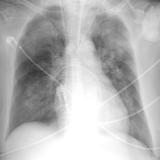

APE 1

Date: 11/05/2005

Views: 4196